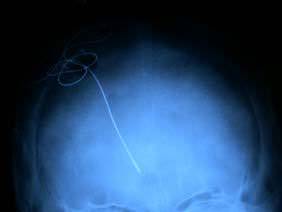

RX de control tras colocar un electrodo para estimulación cerebral